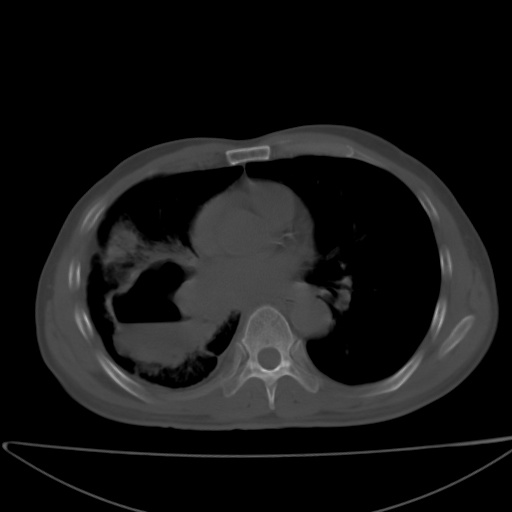

以下是引用jsgdoctor在2008-11-6 22:12:00的发言:[br]右主支气管壁明显增厚,管腔狭窄.考虑为右侧中央型肺癌伴阻塞性炎症\\肺脓肿.

以下是引用zjzjr在2008-11-6 20:25:00的发言:[br]中心型肺ca,合并阻塞性肺炎

以下是引用zsl6918在2008-11-6 19:43:00的发言:[br]右侧中心性肺癌(鳞癌)